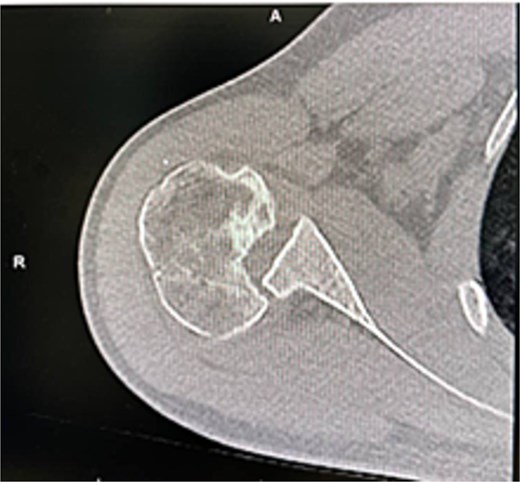

X-rays and CT confirmed missed locked posterior dislocation with healed comminuted fracture and large reverse Hill-Sachs lesion. MRI revealed posterior shoulder dislocation, reverse Hill-Sach’s lesion (Fig. 2) around 2.5 cm in diameter and 1.7 cm in depth, posterior labral tear, and secondary avascular necrosis.